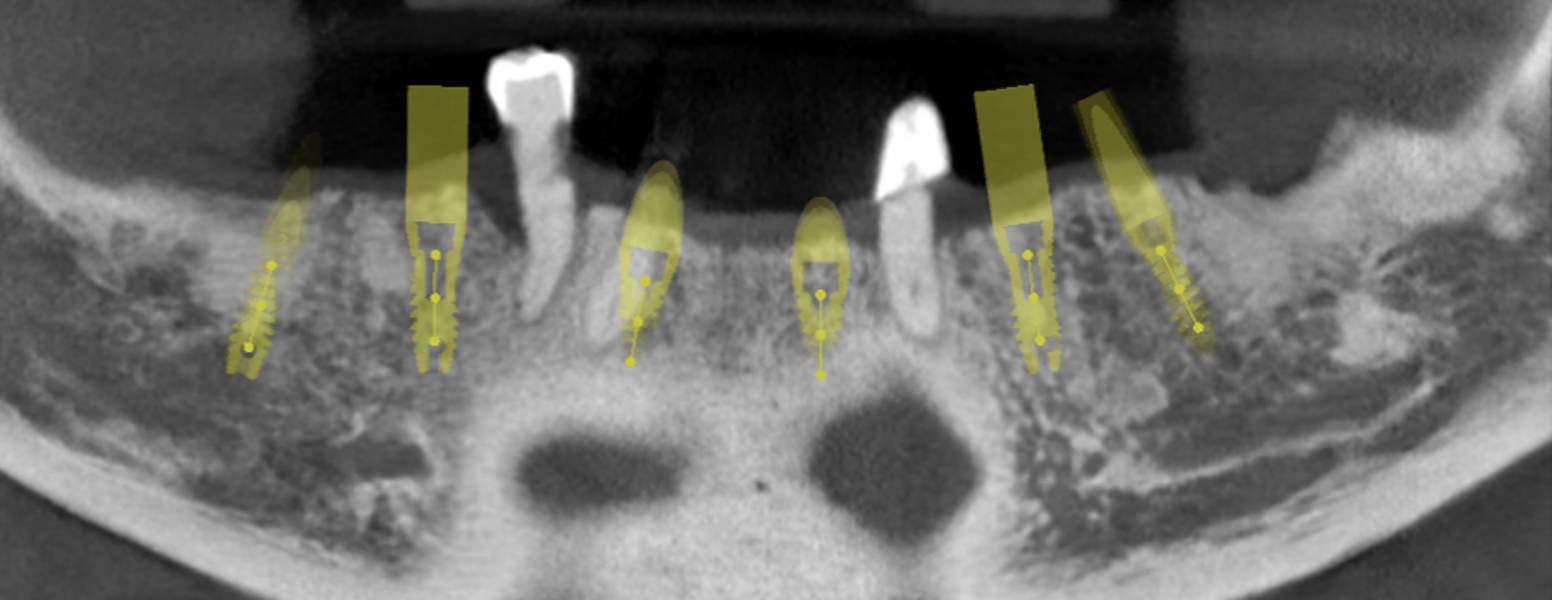

Le projet esthético-fonctionnel avant la mise en place d’implants reste la pierre angulaire du plan de traitement, il permettra de réaliser un guide scanographique, et éventuellement un guide chirurgical. Ce projet formera l’enveloppe externe de la future prothèse, qui sera stockée dans le logiciel de CAO. Les techniques numériques ont permis de simplifier et de perfectionner cette étape ; de même ells réduisent le temps de la prise d’empreinte pour la pose du bridge provisoire. L’empreinte numérique sur les scan bodies sera réalisée avec la prise d’occlusion. Elle sera instantanément transmise au laboratoire, qui l’ajoutera comme calque supplémentaire au fichier CAO du patient. Le design de la prothèse pourra rapidement être établi. Il en découlera la fabrication d’un bridge monolithique vissé comportant des bagues de collage en titane collées à l’intrados, ou d’une prothèse scellée directement sur les piliers implantaires. Nous savons tous que le comportement biomécanique de nos bridges est influencé par de multiples facteurs : espace interarcade disponible, nombre d’implants, forme de l’arcade, matériaux prothétiques, forces occlusales fonctionnelles et parafonctionnelles.

Inconvénients des PMMA : Leurs propriétés mécaniques sont trop éloignées de celle de l’os, en effet le module élastique du PMMA est très faible, rendant illusoire la contention des implants fraîchement posés (Fig. 2). Ceci est confirmé par la photogrammétrie. L’expérience suivante a été réalisée ; un provisoire est réalisé en PMMA seule, à partir d’une empreinte optique intra-orale et une photogrammétrie.

Ce bridge provisoire est porté entre dix et vingt semaines. Une nouvelle empreinte optique et photogrammétrie sont réalisé à nouveau sur les piliers implantaires. Les positions des piliers implantaires ne sont pas superposables ;les implants ont migré dans les zones de moindre résistance. Il était donc necessaire de renforcer ce PMMA.

Différentes techniques analogiques ont été employées, de la grille métallique noyée dans la résine acrylique au renfort en CrCo coulé. Ces techniques sont chronophages, et coûteuses de surcroît. Nous utilisons maintenant pour nos MCI un nouveau matériau compatible avec le flux numérique : Le Zantex. C’est un polymère dense renforcé en fibre de verre bi bidirectionnelle (Fig. 3). Le matériau est compose d’une matrice en résine (25 %) renforcée par un réseau de fibres de verre (75 %). Le réseau de fibres tridimensionnel à motif croisé a été conçu de sorte que son module élastique de 35 GPa est environ dix fois celui du PMMA, et sa resistance à la traction est supérieure à celle de la zircone ! Il se présente sous forme de disque compatible avec les usineuses du marché (98 mm de diamètre, et disponibles en différentes épaisseurs).